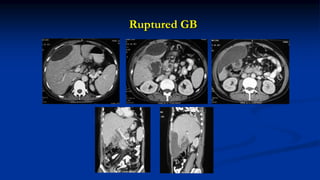

Ruptured GB

Gall stone eroding & causing Pseudoaneurysm